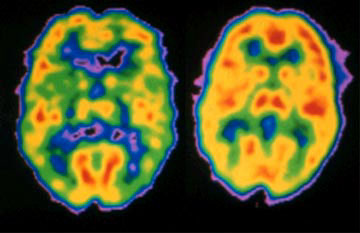

I’ve got a piece about depression and creativity in the latest Griffith Review, Essentially Creative. The piece explores the links between mood disorders and creativity, and asks what we’re losing when we define behaviours intimately connected with creativity as disorders. It’s also a very personal piece, and one I found quite confronting to write.